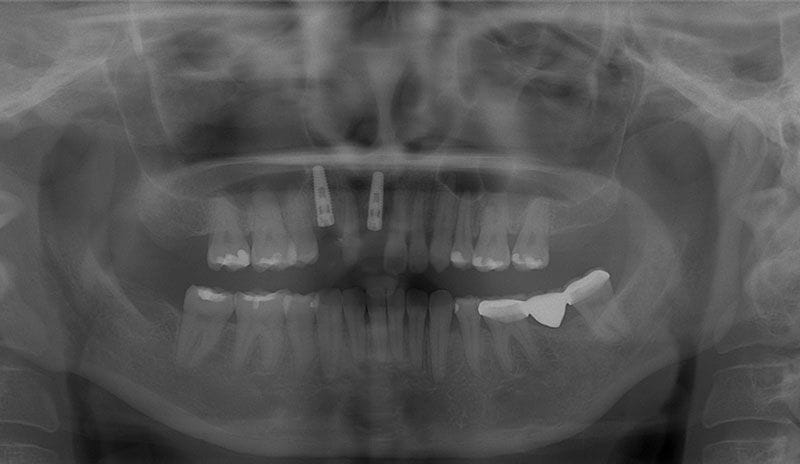

術前X光片